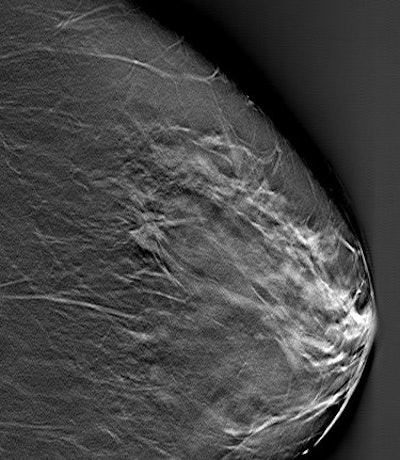

![]() |

| Above, a DBT study in CC and MLO view with a dramatic lesion. Below, DBT study in CC view with two lesions at two different levels. Images courtesy of Dr. Laurie Fajardo, Breast Imaging Research, University of Iowa, Iowa City. |